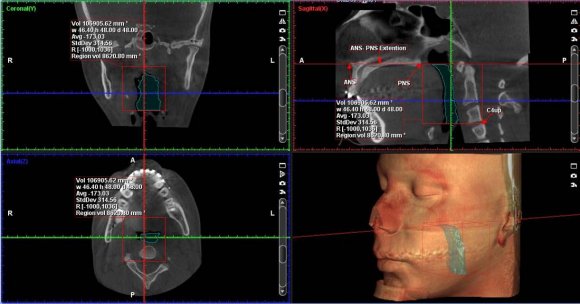

The airway could be isolated after demarking the total volume of interest required for the study. The ROMEXIS software automatically created the third dimension based on the height and the width of the region marked in the two-dimensional view (Figure : 2). Using the 3D region growing tool, the 'air cavity' was selected from the pre-sets. A local threshold level of 70 was used and the particular area of interest in the airway region was selected. This procedure was carried out by a single operator (S.K) to create and measure the rendered volumes. For reliability purpose, it was repeated by the same operator after a period of two weeks and finally, the average is taken for the calculation.

The descriptive statistics are summarised in Table-I, II shows the changes in the cephalometric measurements of the craniofacial morphology taken before and after the mandibular advancement surgery. The volumetric increase in the Pharyngeal Airway Space (PAS) for the patients (n=7) showed a significant increase from baseline (T0) to 3 months post-surgical (T1) (t=4.51, p=0.04 < 0.05), which is represented in Table-III. From baseline (T0) to the post-surgical measurements (T1), the total PAS volume for a mean mandibular advancement of 4.7mm showed an increase of 28.29%.Changes in the PAS volume before and after mandibular advancement surgery (volume in mm3) are given in Figure : 5-7.